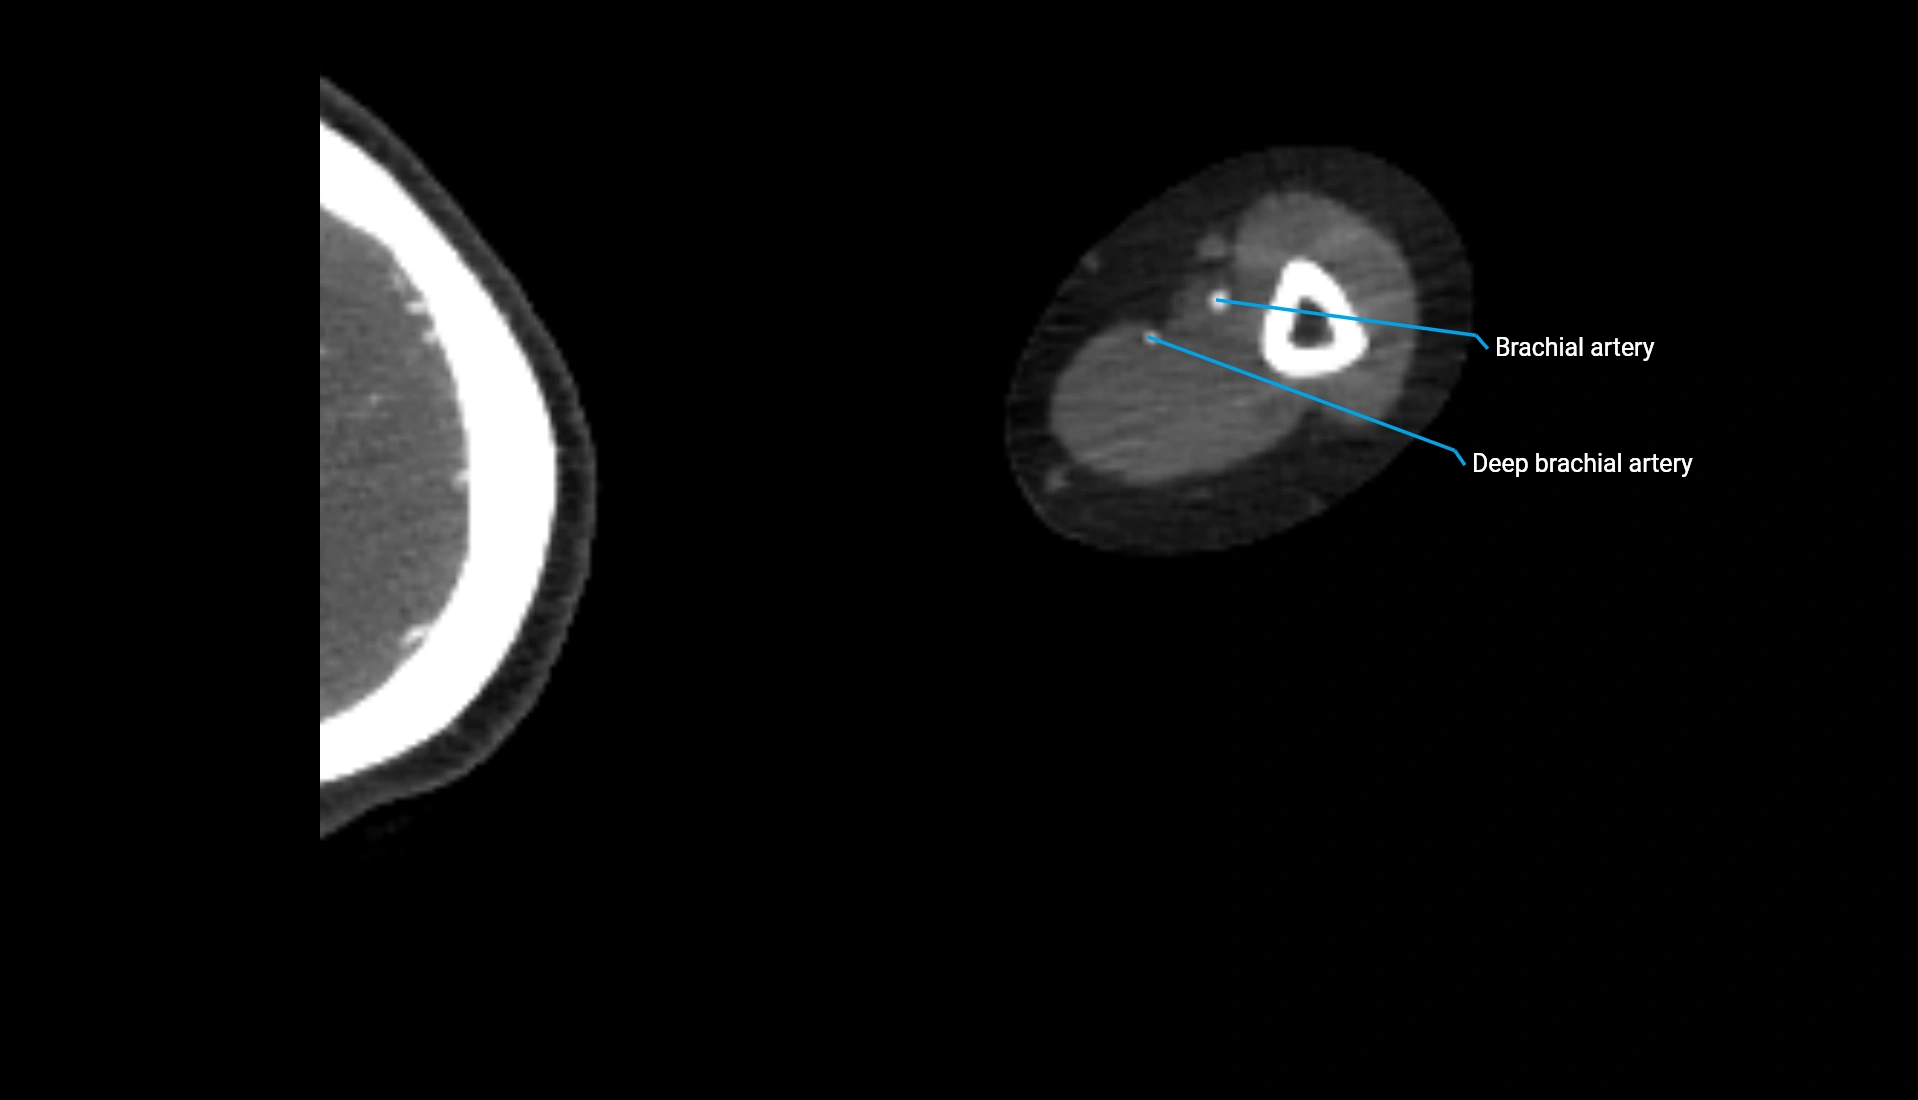

MRI image

image